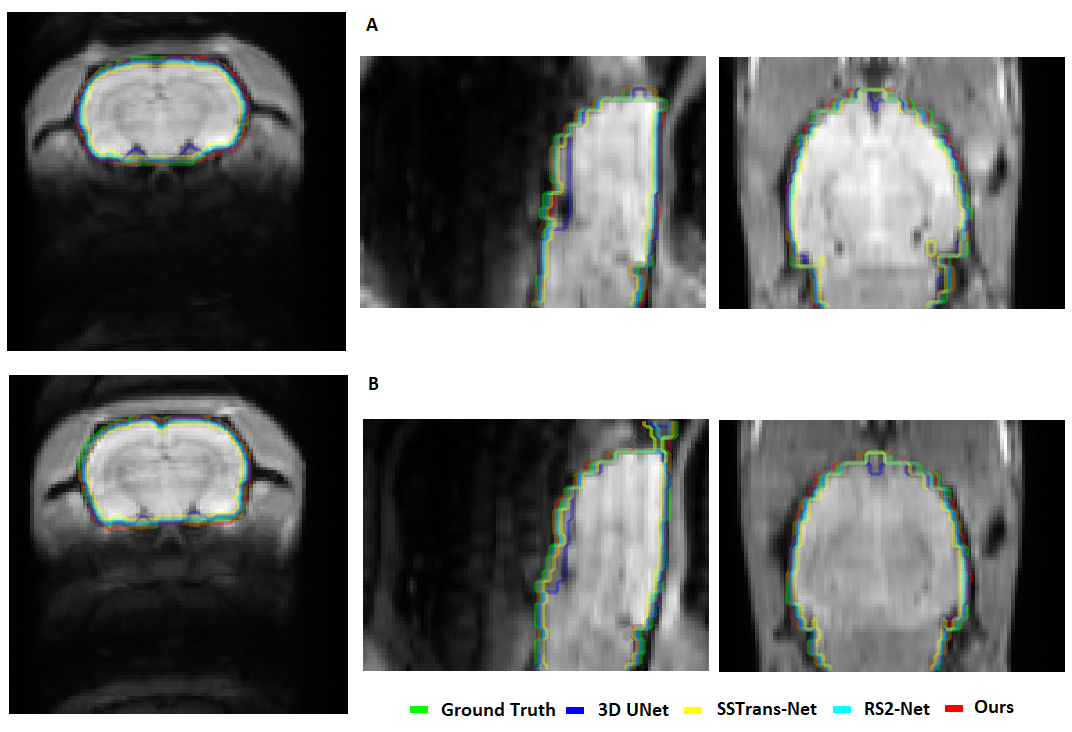

Figure 4: This figure presents the skull-stripping results across various CTNI datasets (A, B: dataset 1- C: dataset 2, D: dataset 3). The red region indicates the manually annotated ground truth, while the areas outlined in different colors correspond to the results produced by different methods.

Refer to caption

Figure 5: This figure presents the skull stripping results for two fMRI samples from dataset 1 in three differnt views (Axial, Sagittal, and Coronal). The light green region indicates the manually annotated ground truth, while the areas outlined with different colored lines correspond to the outcomes from different methods.

To evaluate the performance of our proposed method, skull stripping results from two subjects in the dataset 1 test set are presented in Figure 4A and B, showing slices from both the middle and back regions of the brain. Additionally, results from a single slice of one subject from dataset 2 and dataset 3 are illustrated in Figure 4C and D. As shown in Figure 4, RATS tends to misclassify non-brain tissues as brain, whereas all deep learning-based methods effectively extract brain tissues. Further comparisons of deep learning-based methods applied to two fMRI samples from dataset 1 are visualized in Figure 5, offering three different views for a more comprehensive assessment.

The Dice metrics for each slice, reported in Table 3, provide a quantitative comparison of the methods. These results highlight that our proposed method outperforms existing techniques and offers a reliable solution for preclinical skull stripping.

Table 3: Dice metric values related to Figure 4 and Figure 5, samples A and B are from dataset 1, sample C, and sample D belongs to dataset 2, and 3 respectively.

Figure 4

Method Sample A Sample B Sample C Sample D

RATS 0.9012 0.8756 0.8667 0.8979

3D UNet 0.9536 0.9427 0.9384 0.9415

SSTrans-Net 0.9712 0.9678 0.9542 0.9654

RS2-Net 0.9751 0.9697 0.9567 0.9686

SST-DUNet(ours) 0.9819 0.9781 0.9687 0.9773

Figure 5

Method Sample A Sample B

3D UNet 0.9519 0.9504

SSTrans-Net 0.9642 0.9617

RS2-Net 0.9661 0.9654

SST-DUNet(ours) 0.9765 0.9749